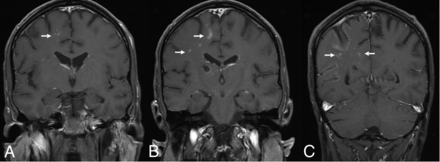

Under the World Health Organization Classification of Hematolymphoid Tumors (2022), LG is an LPD occurring exclusively in immunocompetent patients. Brain involvement is reported in up to 30% of patients with LG and is often secondary, with sporadic primary CNS involvement.49 Brain lesions may be diffusely infiltrating or masslike and show nodular, perivascular, or ringlike enhancement. Subependymal extension or leptomeningeal involvement may be present (Fig 4). LG typically exhibits an angiocentric and angiodestructive infiltrate consisting of lymphocytes, histiocytes, and sporadic plasma cells, with rare neutrophils and eosinophils. Necrosis may be observed in higher-grade lesions, while well-formed granulomas are not seen. The differential diagnosis for LG includes CNS lymphoma and vasculitis.50,51 Imaging findings are nonspecific and overlap with multiple tumoral and nontumoral pathologies, including glioblastoma, vasculitis, and chronic lymphocytic inflammation with pontine perivascular enhancement responsive to steroids (CLIPPERS).50⇓⇓⇓-54 Treatment options include observation, resection, chemoradiation, corticosteroids, interferon, immunoglobulin, and rituximab.54

EBV lymphomatoid granulomatosis. A 40-year-old man with a history of HIV. EBV lymphomatoid granulomatosis was the finding of a prior right thalamus biopsy. Lymphohistiocytic infiltrate was the finding of a biopsy, consistent with EBV-associated lymphoproliferative disorder. Coronal T1-weighted postcontrast images show linear and punctate enhancement foci in the left parieto-occipital lobes (arrow).